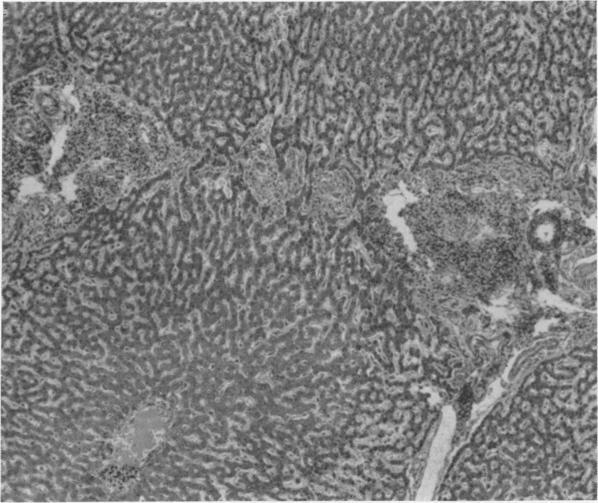

Ischemia potentiating cryosurgery of primate liver.

Ann Surg. 1971 Aug;174(2):309-18. doi: 10.1097/00000658-197108000-00019.